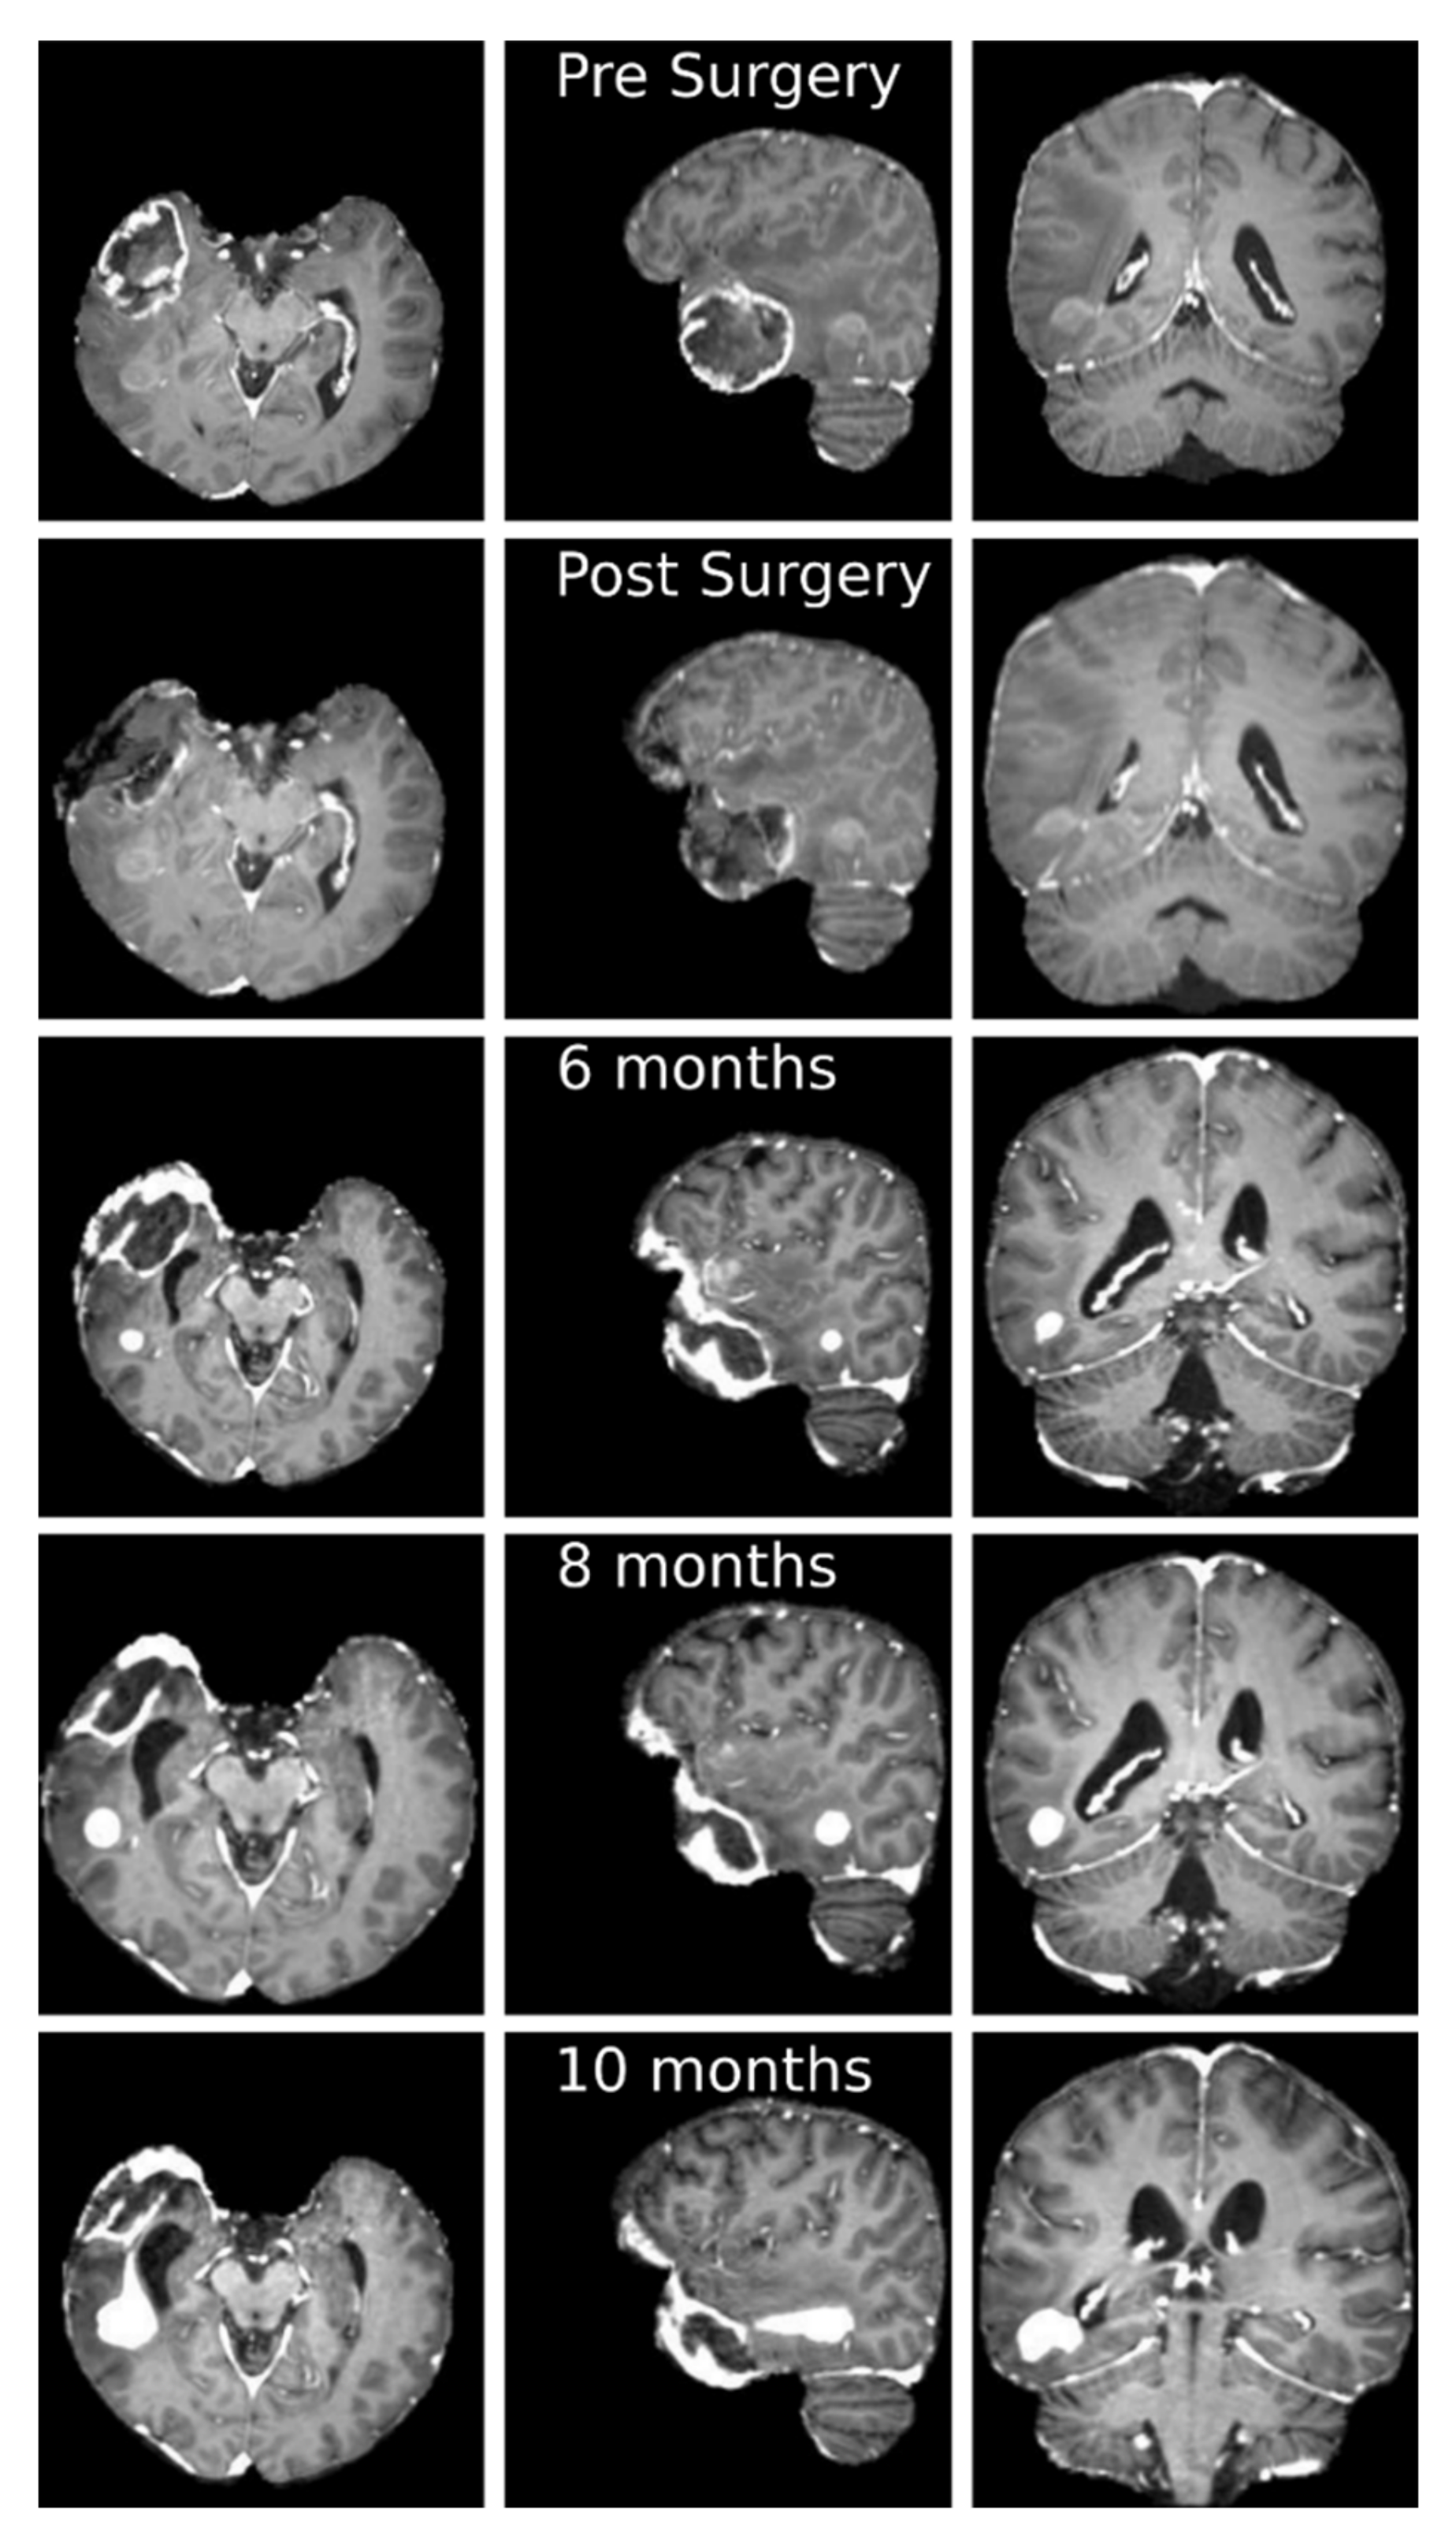

3.3. Clinical Case Study: Primary GBM Tumor